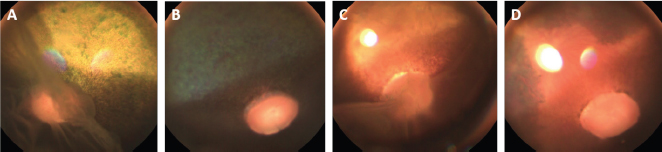

A giant retinal tear and partial disinsertion of the dorsal retina were observed OS. The retina was completely detached and radiated from the rim of the optic disk in transparent folds extending towards the posterior lens surface. The torn dorsal end of the retina had a typical scrolled and wrinkled appearance. These features were consistent with a rhegmatogenous retinal detachment (RRD).

The ophthalmic examination of the gelding was identical to that of the mare except for a lateral divergent strabismus with a slight rotation of the globe within the orbit OU regardless of head positioning. The ventronasal sclera were continuously exposed (Fig. 2A and B). The equator of the lens was visible OU after pupil dilation, and an incipient posterior cortical cataract was present OS (Fig. 2C and D). Intraocular pressure measured 27 mmHg OD and 26 mmHg OS.

Fig . 1. Photographs of the fundus of the left eye of case 1 with a retinal detachment, giant retinal tear and partial disinsertion of the dorsal retina (A); normal fundus of the right eye of case 1 (B); subalbinotic fundus of the left eye of case 2 with a retinal detachment, giant retinal tear and partial disinsertion of the dorsal retina (C); normal sulabinotic fundus of the right eye of case 2 (D).